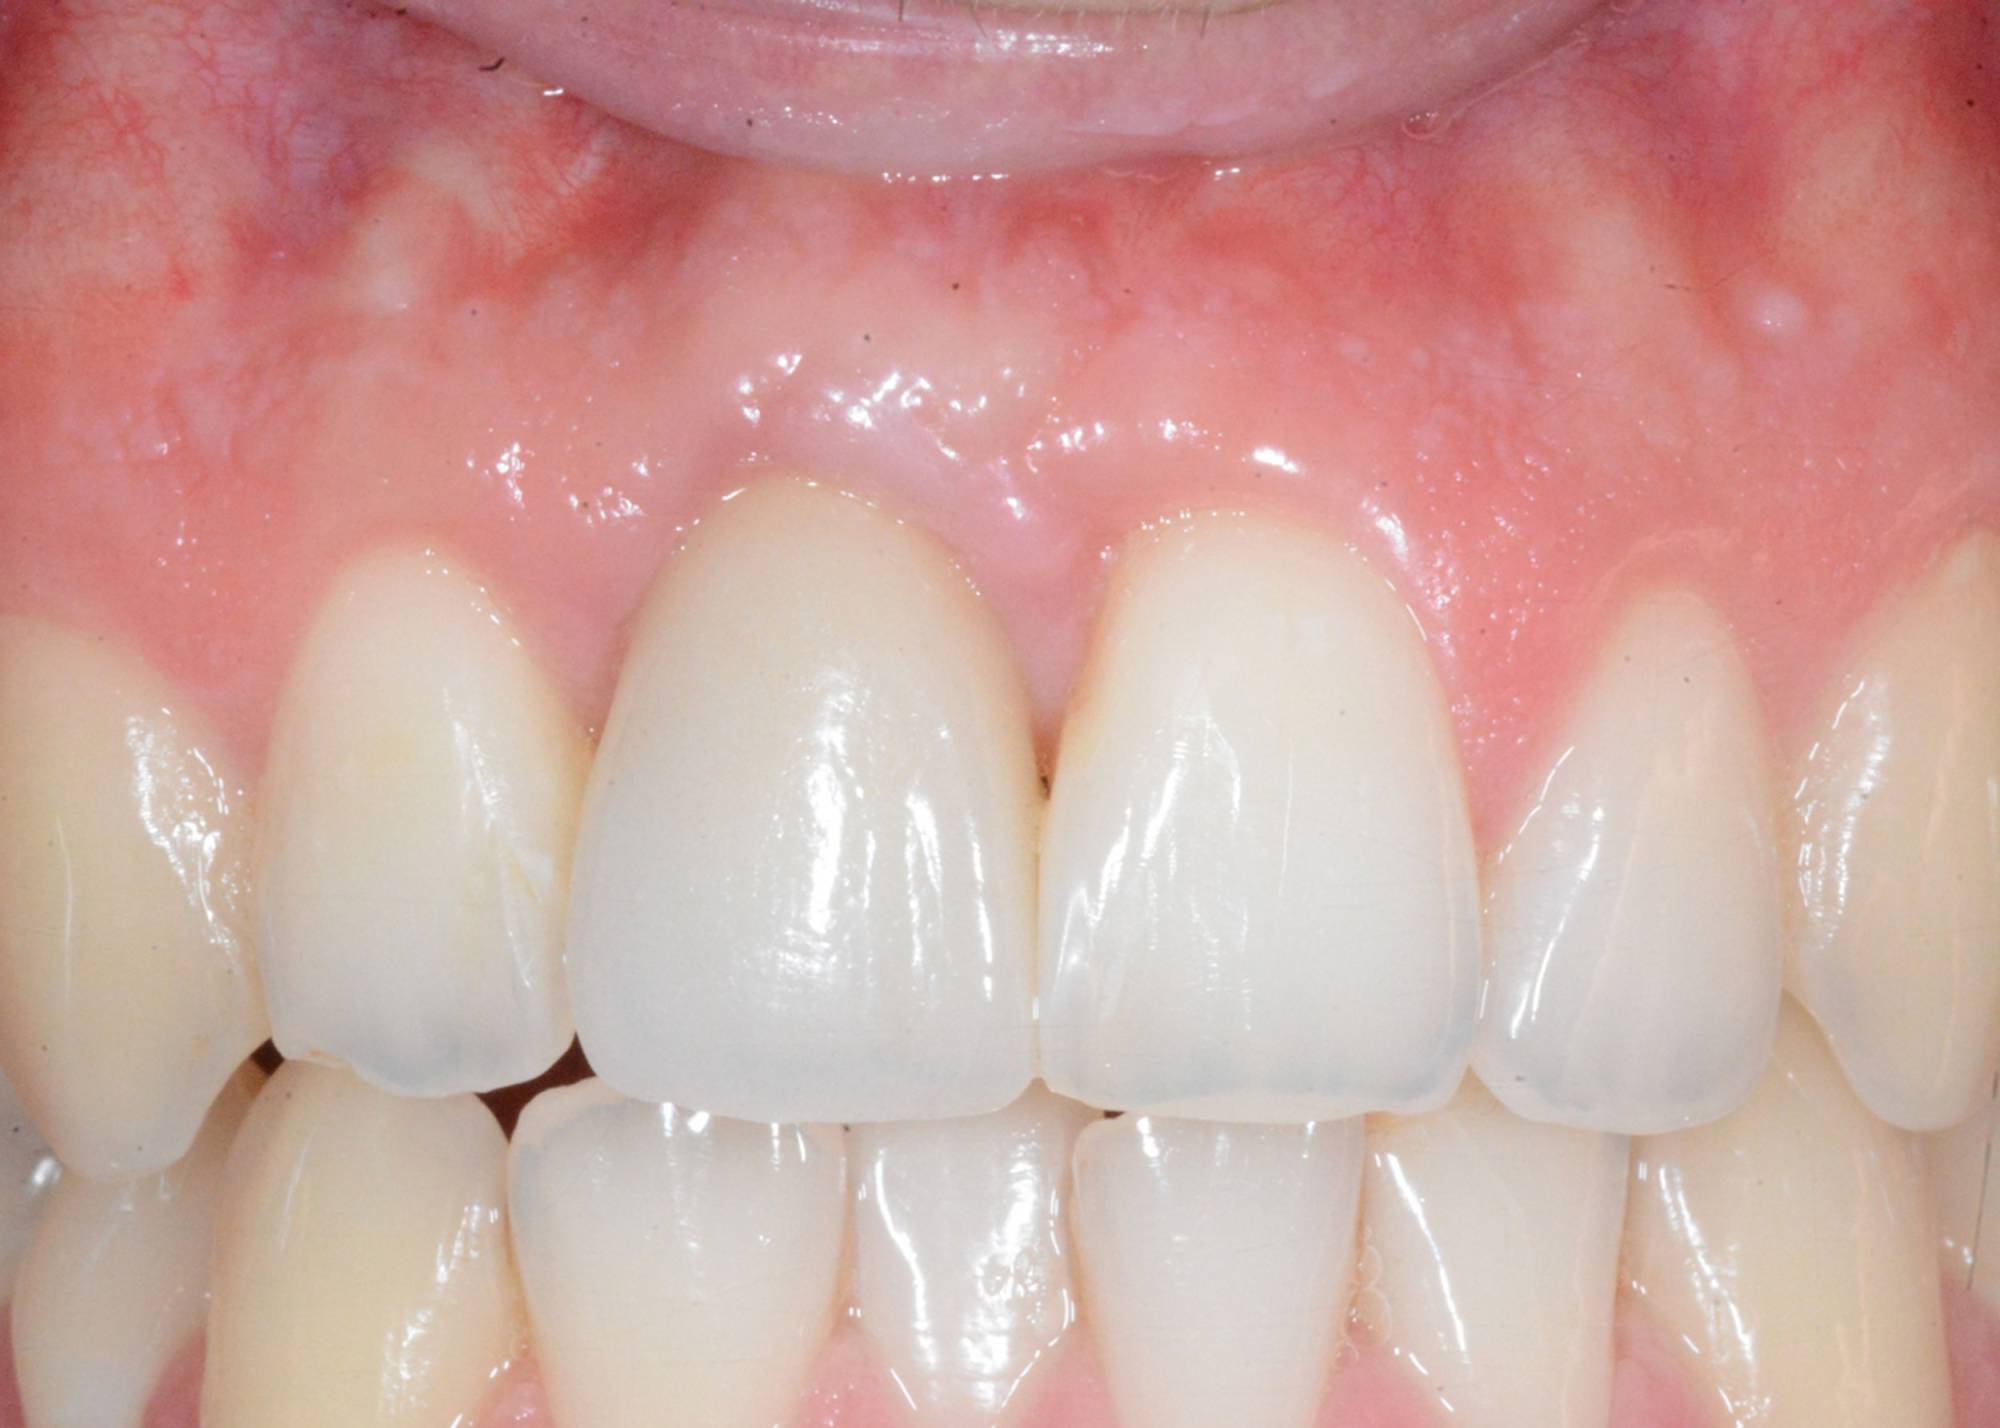

L'impianto dentale osteointegrato è una sorta di radice artificiale che si inserisce nell’osso del paziente, per rimpiazzare un dente mancante.

L'impianto, oltre a essere un metodo sicuro, garantisce l'aspetto esteriore e la piena funzionalità di un dente naturale. Oltre a ciò, mantiene l’integrità dell’osso, non va ad intaccare i denti adiacenti - come invece farebbe un ponte - e migliora l’estetica facciale prevenendo la perdita ossea.

Generalmente devono trascorrere alcuni mesi tra l’intervento chirurgico di inserimento di un impianto e la realizzazione della protesi da fissare ad esso.

In questo lasso di tempo, nel quale l'impianto è sommerso sotto la gengiva e si avvia il processo di guarigione ossea, si realizza l'osteointegrazione, ovvero un intimo contatto fra l’osso e la superficie biocompatibile in titanio dell’impianto.